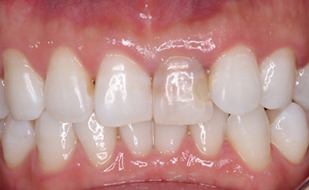

前歯のセラミック症例

| 主訴 | 前歯の色が変色していることが気になる。 (オールセラミック) |

| 年齢・性別 | 30代 男性 |

| 治療期間 | 約3週間 |

| 治療内容 | オールセラミック |

| 治療本数 | 1本 |

| 治療費用 | 仮歯(テック)5,500円(税込) +かぶせ物代 (オールセラミック)110,000円(税込) |

| 治療方針 | ①歯の形態、かみ合わせ等を模型上で 診査、患者さまと相談した上で形態の決定 ②仮歯の装着 ③セラミックの試適(色・形の確認) ④セラミック装着 |

| ドクターのコメント | 治療後はセラミック治療による審美性は 獲得できましたが術前と比べ、 ホワイトニング後の後戻りがあり、 歯が黄ばんできているので、 ホワイトニング後のメンテナンスの 重要性をお伝え致しました。 |

治療過程

- 治療前

- 歯の形成後

- 仮歯装着後(2週間つけていたため変色している)

- 完成前の試適

- 治療終了後